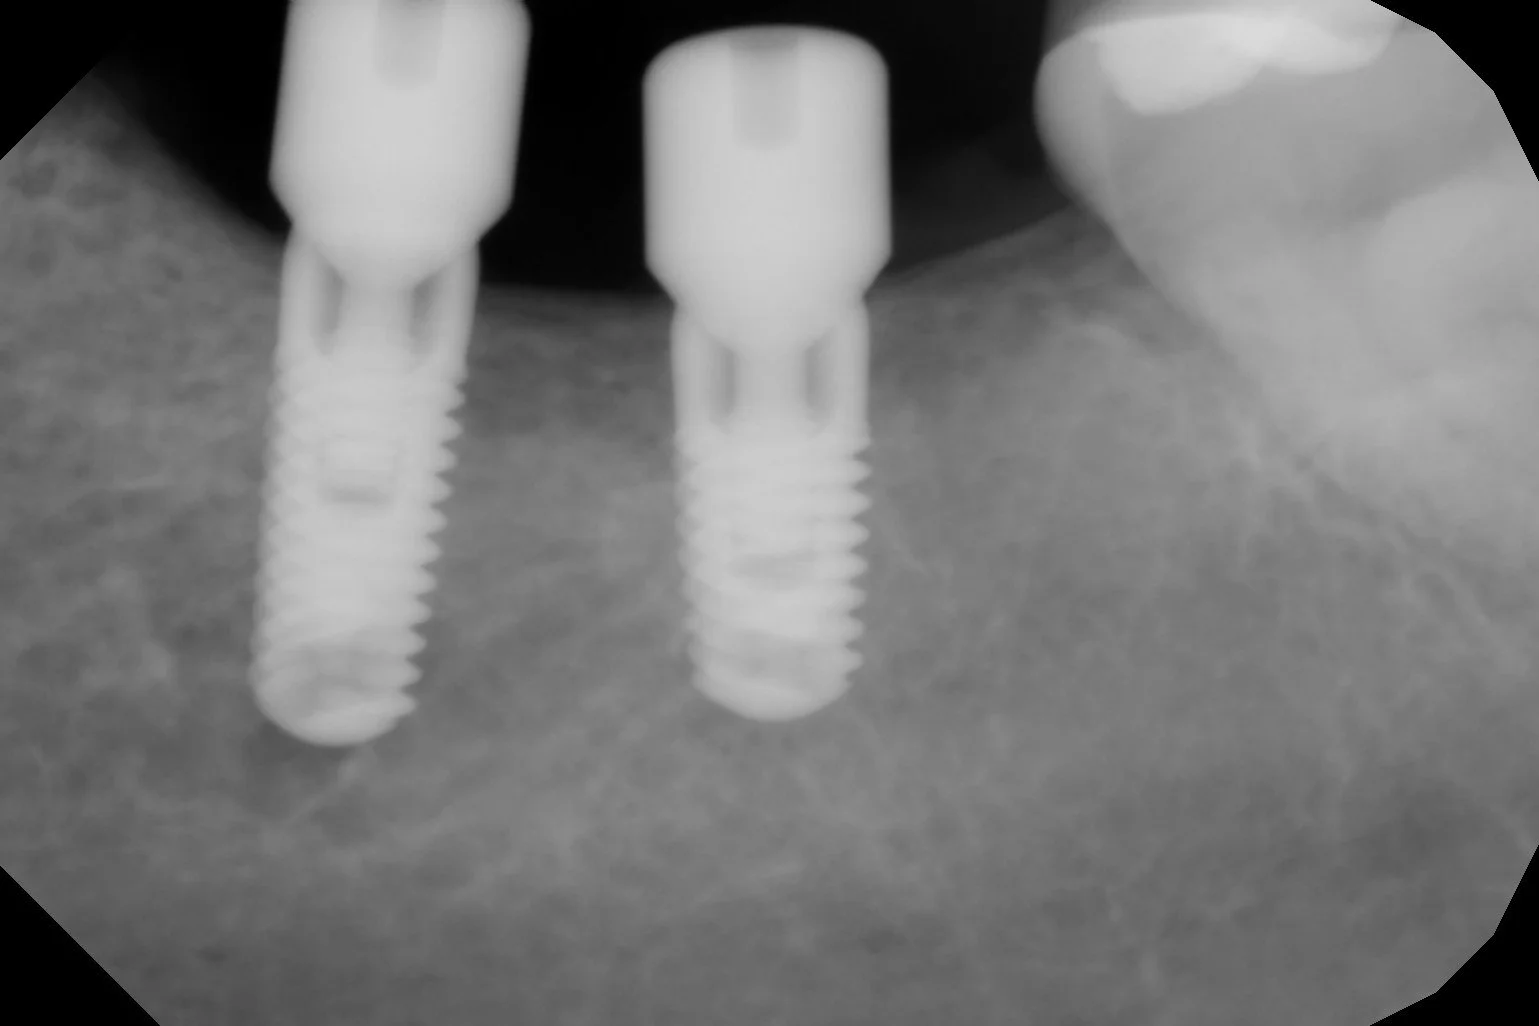

Los implantes son fijaciones de titanio de alta precisión que se colocan para reponer uno o varios dientes y sirven de "raíces artificiales" donde fijar una prótesis dental.

Después de un examen clínico y radiológico con CBCT en 3D, el cirujano le puede indicar si usted es candidato a este tratamiento.